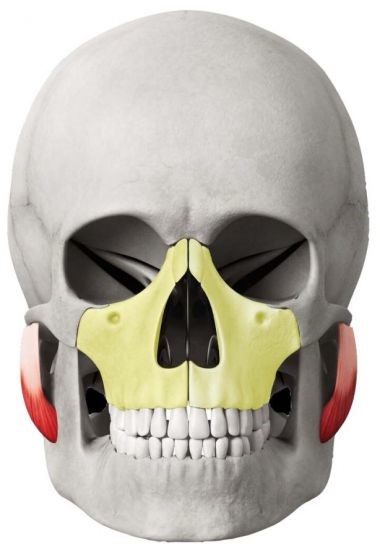

CƠ HÀM SỰ LIÊN QUAN MẬT THIẾT

Phần cơ màu đỏ là cơ hàm, nó kết nối xương Maxilla với hàm dưới và đó là lý do tại sao khi Maxilla cao thì hàm dưới sẽ cao và hướng ra ngoài (không bị lẹm) tạo nên đường jawline - quai hàm rất đẹp.

Ở thế giới hiện đại ngày nay, đồ ăn đã được nấu chín kĩ hơn, dễ nhai hơn và xu hướng sử dụng nhiều thực phẩm dạng mềm chứa nhiều dinh dưỡng hơn như sữa, phô mai, trứng... điều này khiến cơ hàm ngày một thoái hoá dần. Việc lười nhai như đã đề cập ở trên cũng dẫn tới vị trí của xương Maxilla không đúng.